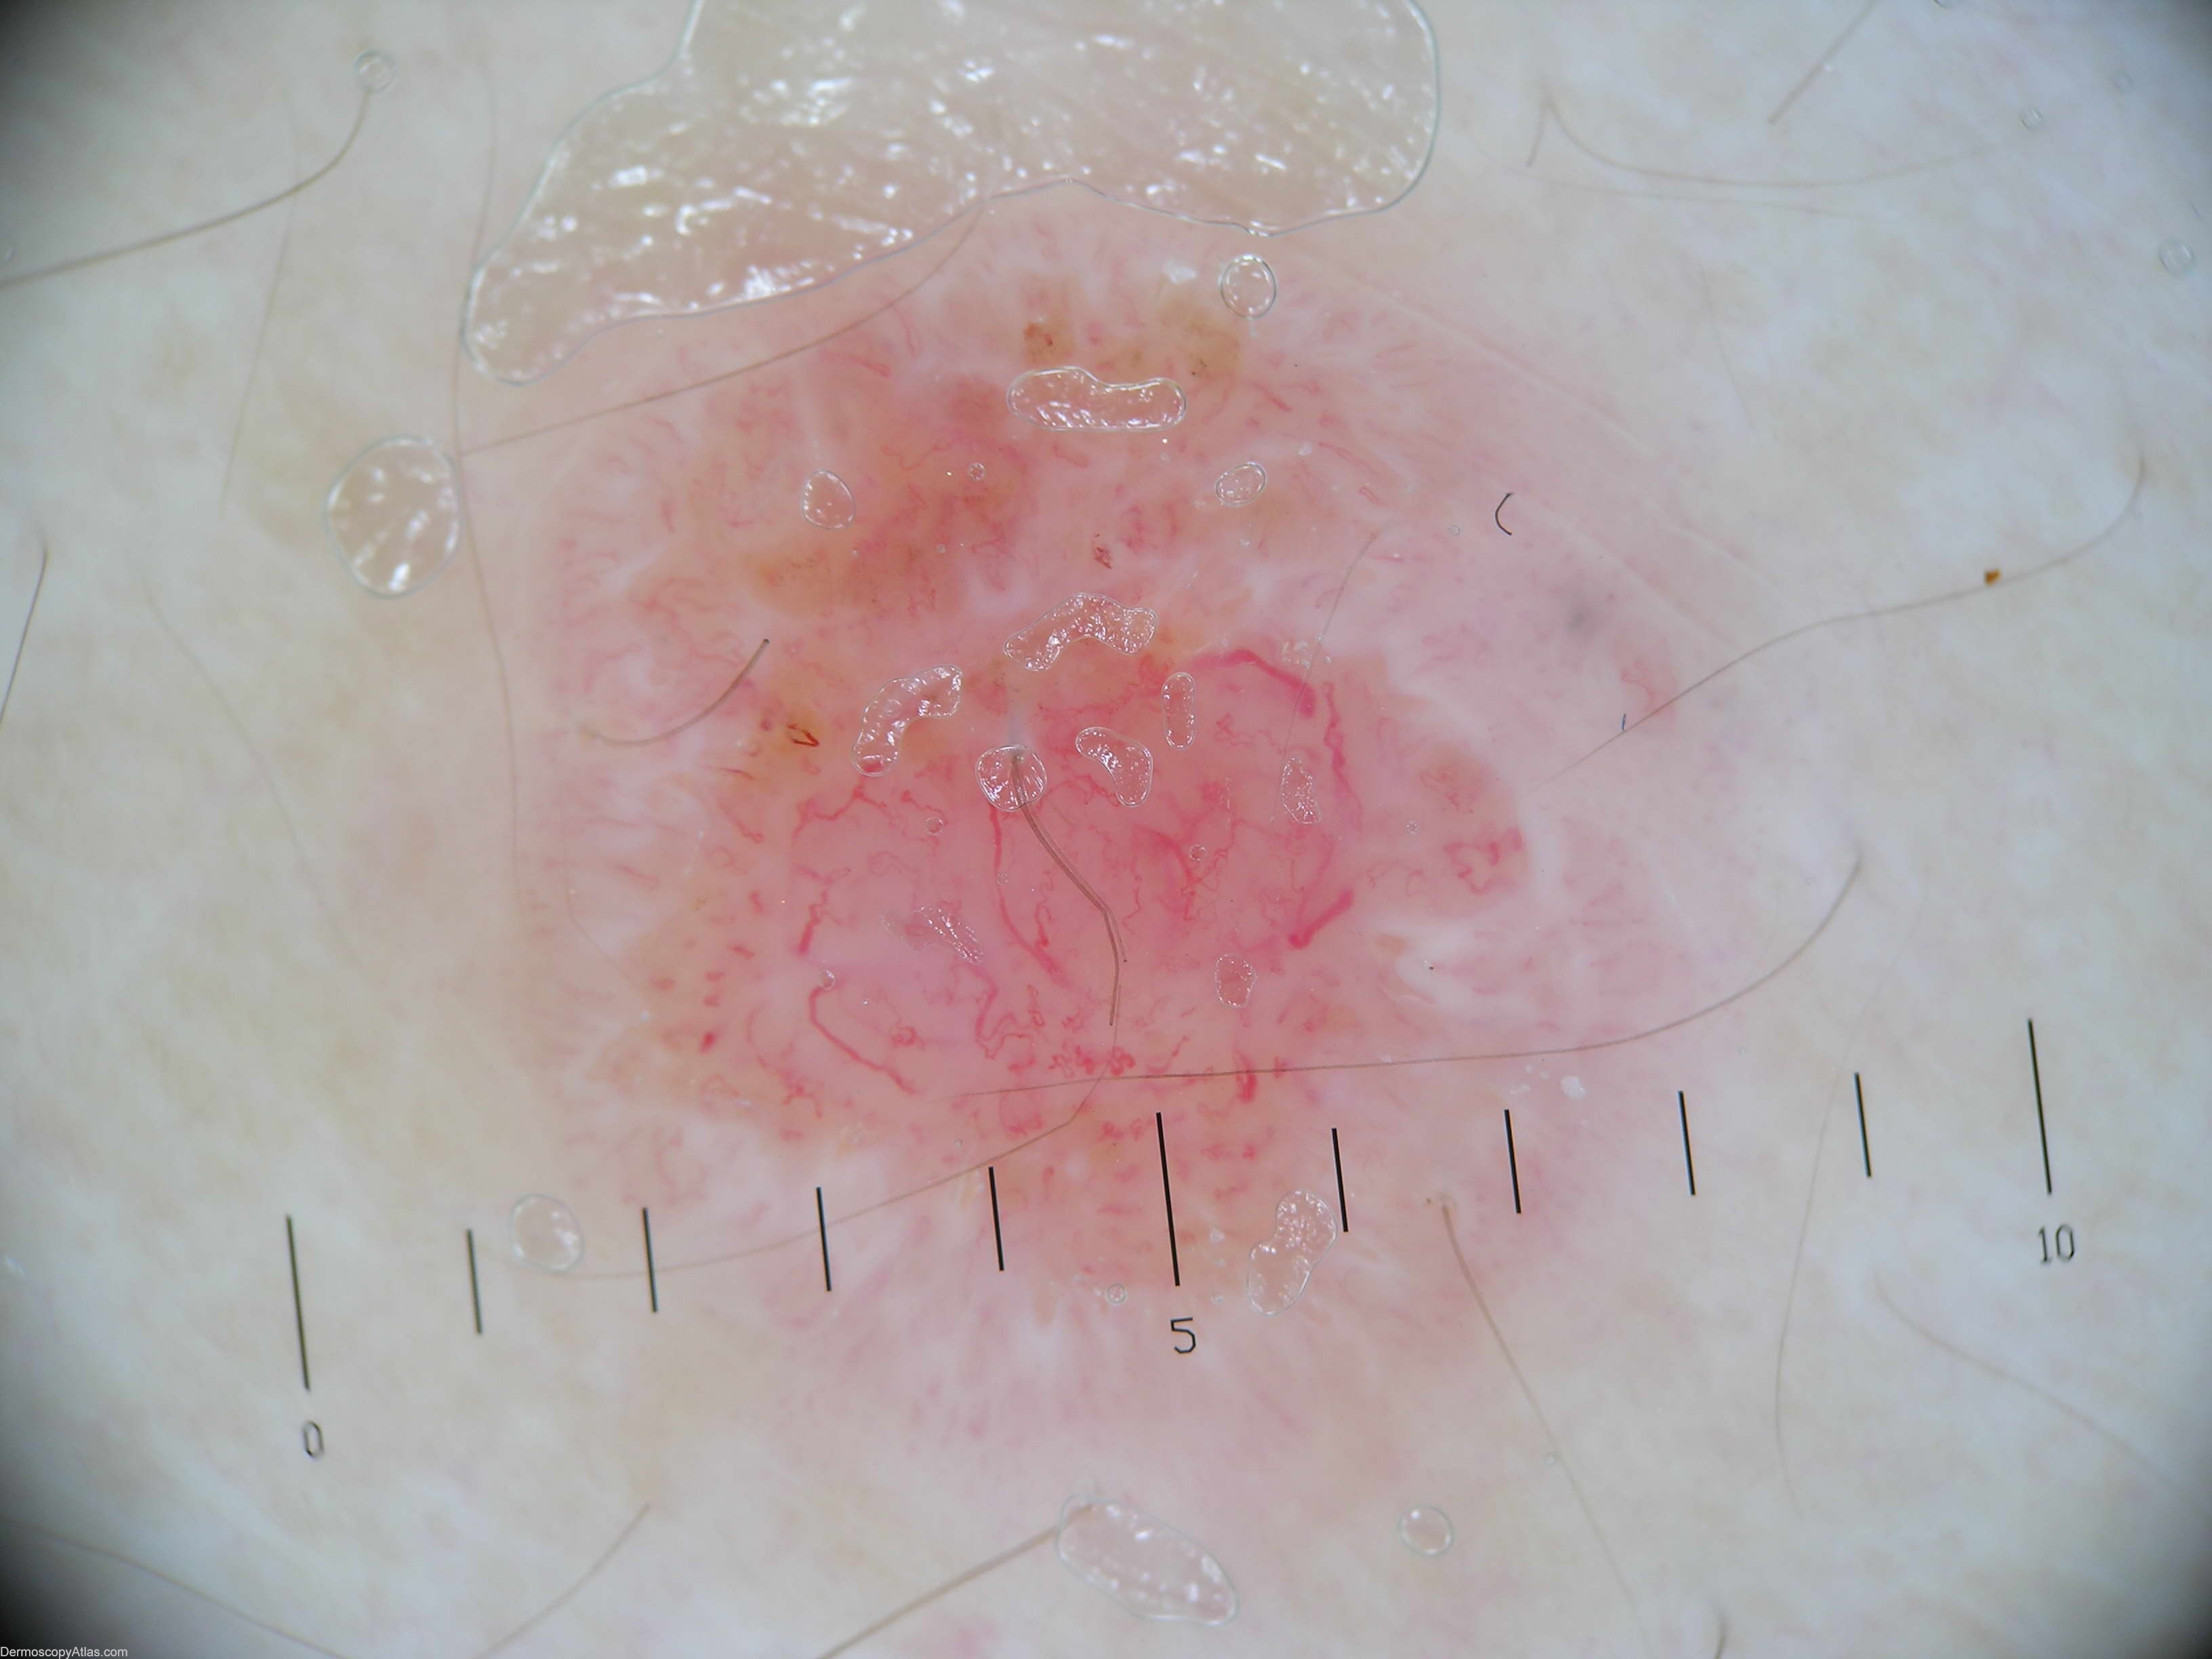

Image Number #3077 (Melanoma amelanotic)

Site: Leg

Diagnosis: Melanoma amelanotic

Sex: F

Age: 21

Description: Pink nodule on leg The author MD, PhD Dmitry Sokolov

From words of the patient this lesion of skin of the leg has appeared 2 years ago and gradually increased in size. Last year is marked by an itch in a zone around the lesion. The pathology showed an amelanotic melanoma: Breslow 1.75, Clark II     The author MD, PhD Dmitry Sokolov